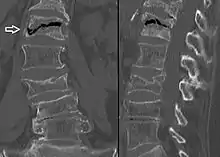

Compression fracture of the fourth lumbar vertebra post falling from a height.